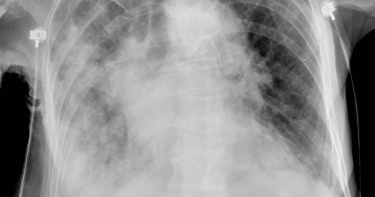

大S猝逝/大S疑因「大白肺」喪命! 醫曝危險性:肺部失去交換氣體能力

女星大S(徐熙媛)春節期間與家人到日本旅遊,卻因流感併發肺炎逝世,享年48歲,引發外界對相關病症的討論。對此,胸腔內科醫師蘇一峰指出,大S疑似因肺炎重症「大白肺」喪命,意味著嚴重肺炎導致呼吸困難,而當嚴重的肺炎時,肺泡裡面會積滿痰液與發炎的水,當肺泡在痰水裡,空氣就無法進入交換氣體,「大白肺其實也就是『病人被自己的痰液水腫活活淹死!』。」蘇一峰今(5)日上午在臉書粉專撰文道,「大白肺」其實是口語名稱,其實就是嚴重肺炎造成呼吸困難,當嚴重肺炎時,肺泡裡會積滿痰液與發炎的水,而當肺泡在痰水裡,空氣就無法進入交換氣體,病人此時用力呼吸,但肺部已失去交換氣體的能力,才會使得血氧仍不斷下降。蘇一峰說,血氧飽和度下降到89%以下就是缺氧狀態,此時應緊急給予氧氣治療,更嚴重時就要插管使用呼吸器,「89%大概可以撐幾小時,如果一直掉到80%,幾分鐘可能就會心跳停止!血氧還沒有掉到60~70,人常常就直接心跳停止了」。至於最近吵得沸沸揚揚的肺炎和敗血症,蘇一峰解釋,2者是「大白肺」疾病的一體兩面,肺炎指的是「肺部因為感染等等原因發炎」,敗血症指的是「因為感染等等原因造成全身性的發炎反應」。他強調,肺炎和敗血症經常同時存在,彼此不是互斥的疾病,「譬如大S就是流感肺炎引起敗血症,肺炎有時候很嚴重來勢洶洶,常一不小心(患者)就過世了」。另外,疾病管制署昨(4)日公布近期流感重症及死亡病例,其中南部一名30多歲男子兩度就醫流感快篩都是陰性,給予症狀治療藥物後返家,但症狀沒有改善,後來急診時出現雙側肺炎,經PCR檢驗確認感染B型流感,雖立即進行插管並收治加護病房,並給予抗病毒藥物治療,仍併發肺部黴菌、多重抗藥性細菌感染,還有氣胸、肺部出血,住院1個月不幸病逝。對此,蘇一峰表示,流感病毒造成重症「大白肺」,病毒會先破壞肺部抵抗力,接著細菌、黴菌進到肺部導致續發性感染,過去許多研究都指出,病毒感染後會增加細菌黴菌肺炎。而那位因流感死亡的男性病人,一開始是流感,續發性的黴菌感染就是主要的死因,如同「小偷先撬開門,壞人跟著進來」。

春節期間,疫情、流感等狀況因人潮聚集,因此加劇。北市聯醫陽明院區胸腔科醫師蘇一峰指出,新冠肺炎過年期間有很多重症大白肺,其狀況相比黴漿菌很嚴重。蘇一峰在臉書表示,目前看起來,新冠Covid過年期間造成很多重症大白肺,內科ICU有兩、三成左右,比起來大肆宣傳的黴漿菌肺炎根本不可怕,重症大白肺還是以COVID為主,這病人努力好幾天目前看起來是救回來了。他也在留言處直言,「大開記者會的黴漿菌,其實沒什麼可怕,反而還是COVID目前很嚴重。」依據疾管署監測資料顯示,今年自1月以來,多種呼吸道病原體同時於社區中活動,類流感及COVID-19疫情現呈上升趨勢或處流行期,依據往年經驗,急診類流感就診人次於農曆春節期間將達高峰,提醒民眾若自身或親友為65歲以上長者、具慢性病史等高危險群,應特別留意健康狀況,並請提高警覺如出現呼吸困難、急促、發紺(缺氧)等危險徵兆,請儘速就醫,並配合醫師指示服藥,以降低併發重症的風險。疾管署提醒,符合新冠XBB疫苗接種資格之民眾,應儘速接種,以及時獲得保護力;莫德納和Novavax兩種廠牌均安全有效,12歲以上民眾可選擇一種廠牌接種, 6個月以上至11歲兒童則依核准適應症,僅限接種莫德納XBB疫苗。接種院所資訊可至疾管署官網「秋冬疫苗專區」或至各縣市官網查詢。疾管署呼籲,民眾出遊、聚會時應落實拱手不握手並注意手部與呼吸道衛生,打噴嚏時應用面紙或手帕遮住口鼻,或用衣袖代替,於室內聚會時注意通風,以降低疾病傳播風險。若自身及親友為65歲以上長者、嬰幼兒、高風險慢性病人及孕婦等疾病高危險群,應特別留意健康狀況,如出現呼吸困難、急促、發紺(缺氧)、意識改變、低血壓等流感危險徵兆應及早就醫。

大陸成都一名35歲設計師確診新冠肺炎後,仍熬夜加班工作到凌晨,最後身體實在受不了,前往醫院就醫,結果在短短2天,病情進入「白肺」狀態,甚至出現呼吸衰竭。醫師提醒,年輕人對新冠病毒不可掉以輕心。根據陸媒《紅星新聞》報導,醫師表示,病患一開始只有發燒症狀,幾天後開始出現胸悶、氣緊,因此就醫;CT顯示,其雙下肺有實變,氧飽和度只有50%左右,而正常人的氧飽和度在95%-99%。醫師說明,患者入院後就被送進加護病房,其病情進展相當快,2天之後就進入白肺狀態,甚至出現呼吸衰竭,經過多日治療,氧飽度才達90%左右。醫師透露,患者本身就長期熬夜,身體免疫力可能就有些下降,而他在感染之後依舊熬夜,本身病毒就會導致人體免疫力下降,在感染之後還繼續熬,就會導致免疫系統崩潰,繼而出現肺部感染,甚至是心肌炎。醫師提醒,這個病例也告訴大家,年輕人對新冠病毒同樣不能掉以輕心。